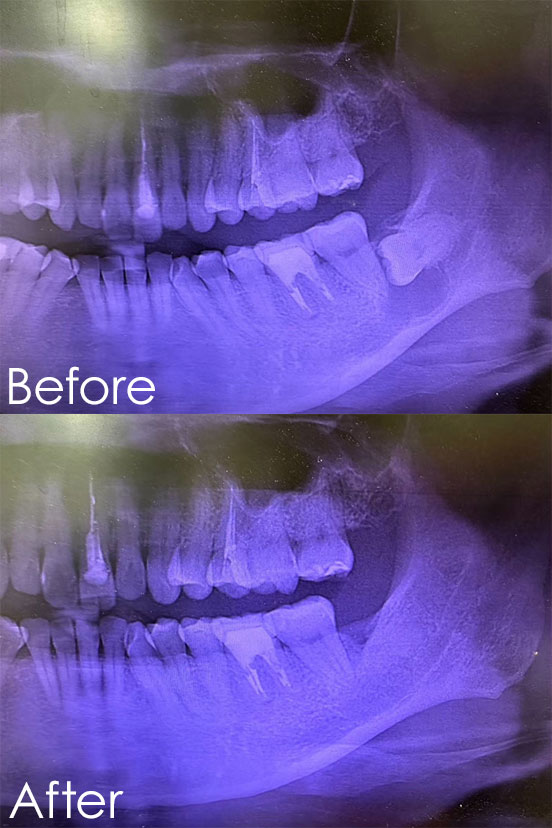

女性Lさん(40代)

お悩み:奥歯がグラグラする。

治療内容:重度歯周病(部分的骨欠損)に対する歯周病治療(再生療法/エムドゲイン)

治療期間:1ヶ月

治療回数:2回

金額:88,000円(税込)

リスク:外科処置となるため術後は痛みと腫れが出る可能性があります。また神経麻痺が出る可能性があります。

再生療法/エムドゲインの特徴:歯周組織再生用材料を塗布する治療で歯周組織が再生されます。